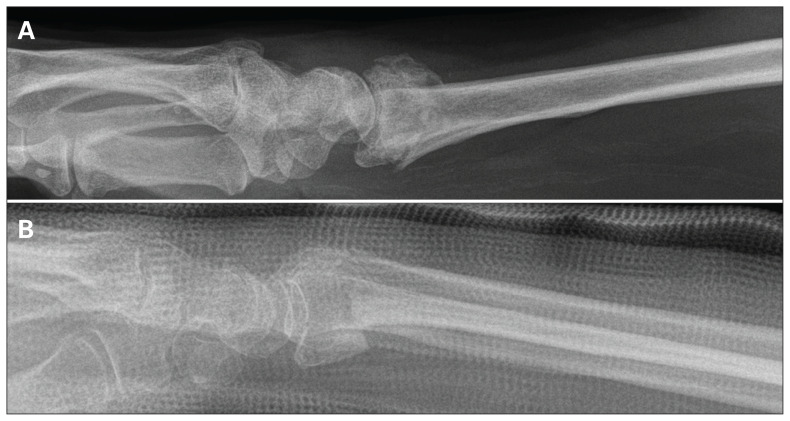

Fig. 7.

Radiographs associated with the lowest and highest standard deviations for measurements of radial tilt. (A) Radiograph 20 was associated with the lowest variation (i.e., it was the easiest to interpret). (B) Radiograph 8 was associated with the highest variation (i.e., it was the most challenging to interpret).